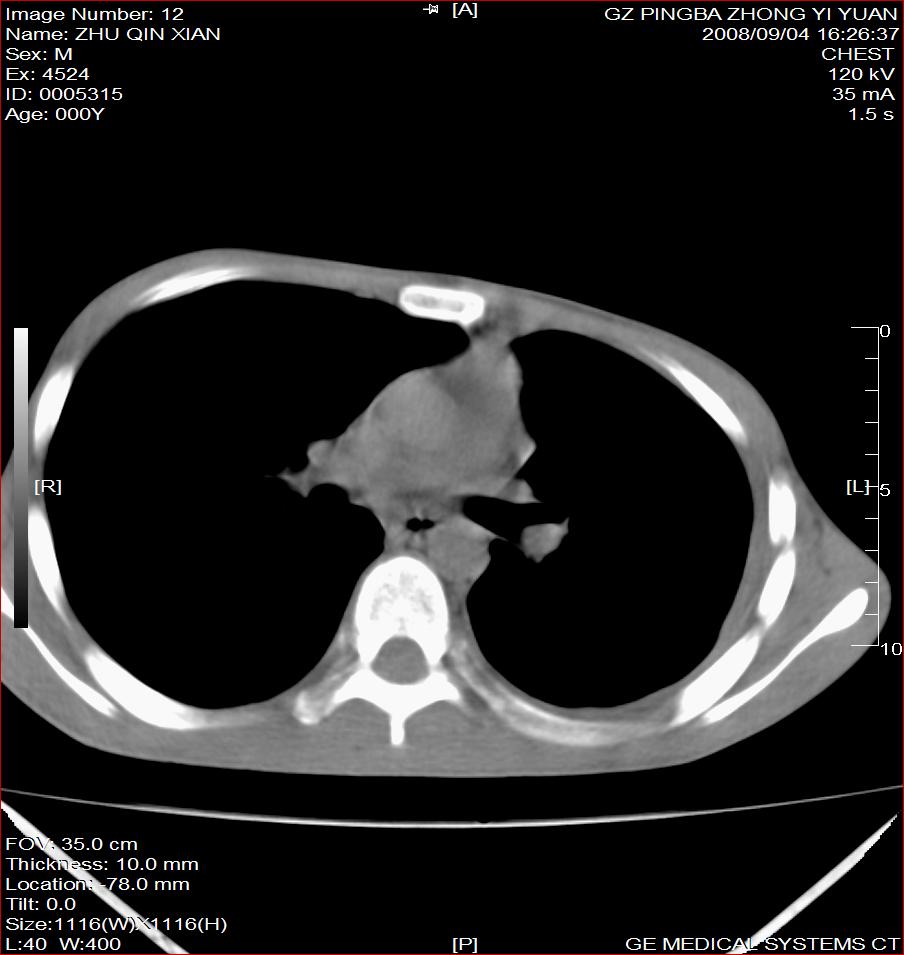

以下是引用随光逐影在2008-9-4 20:05:00的发言:[br]1)考虑两肺结核。2)左侧胸膜炎(胸膜肥厚、粘连,胸腔积液)。3)左侧局限性气胸。

以下是引用子十在2008-9-4 19:34:00的发言:[br]左上肺结核并空洞及双肺播散。节段性肺不张、胸腔积液、胸膜肥厚粘连。[br]